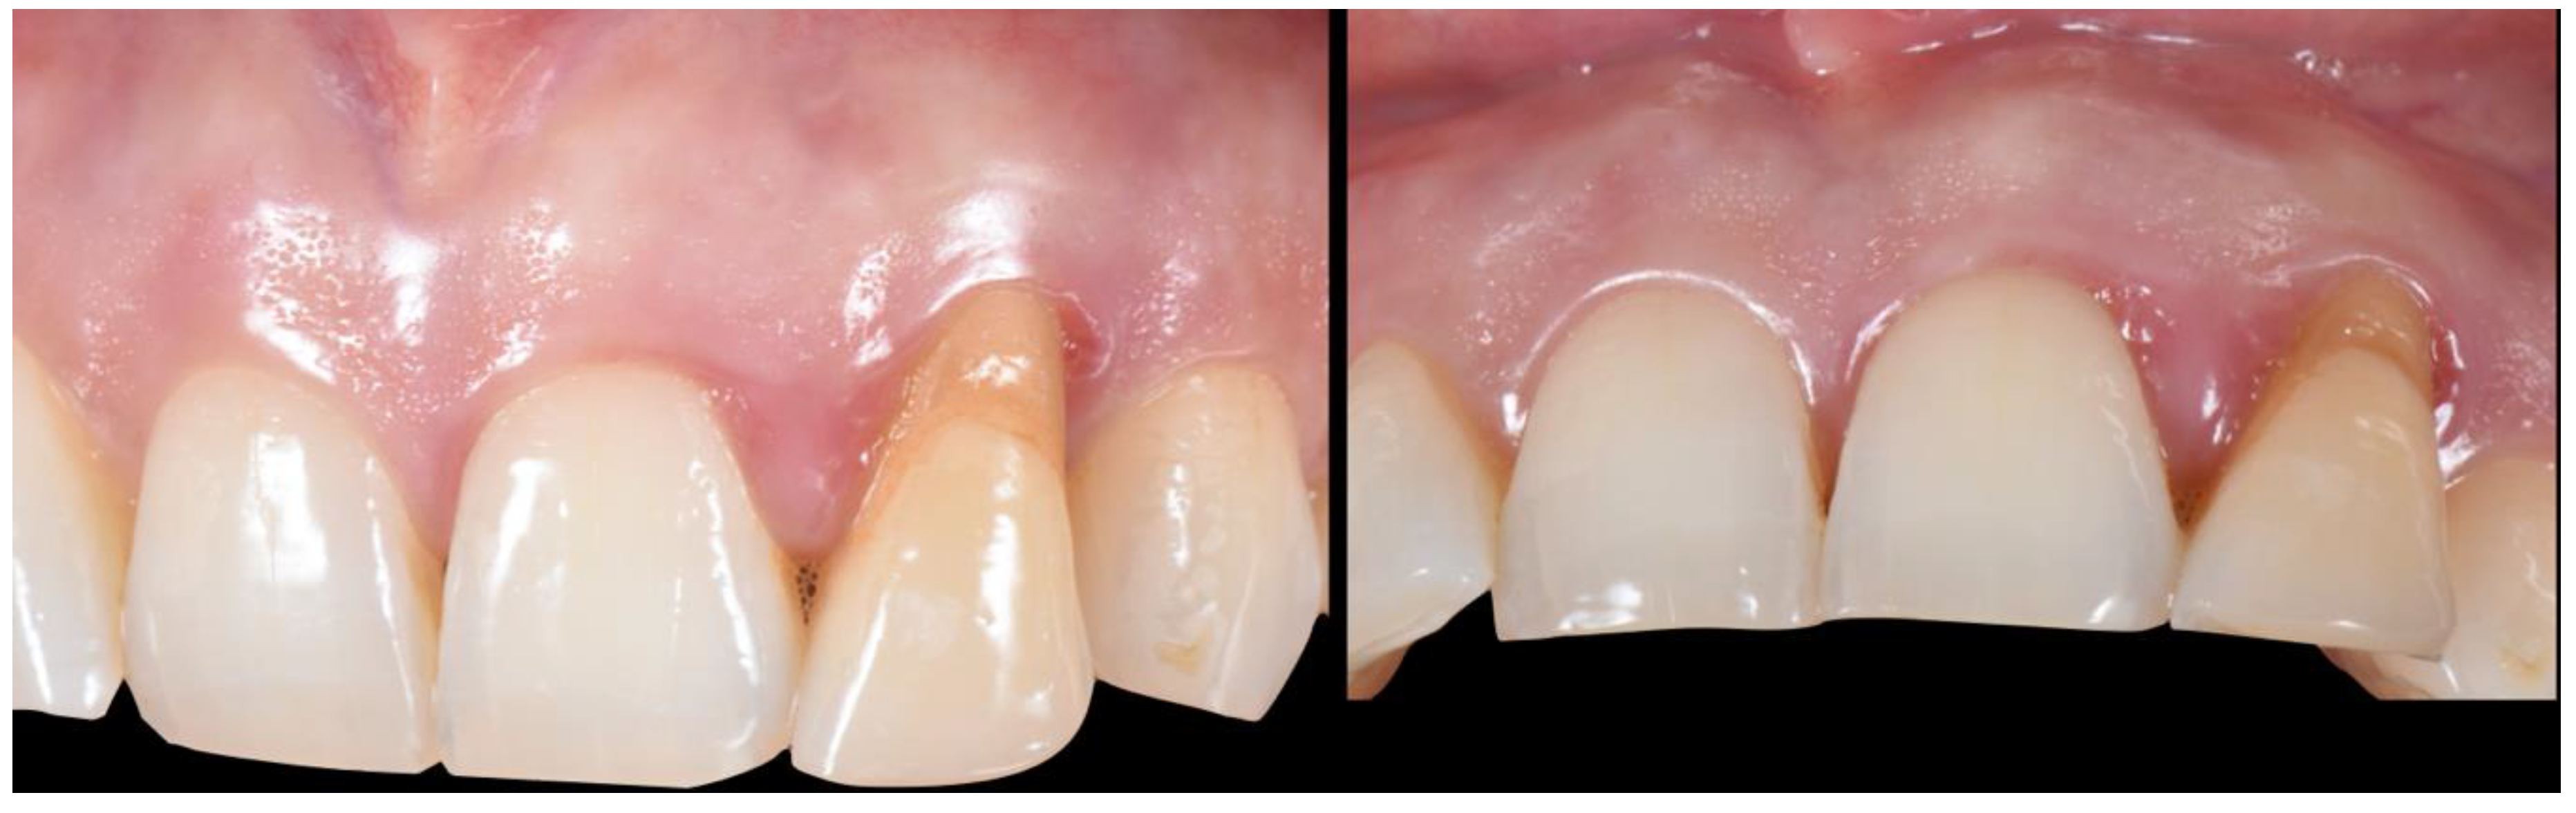

- (A)

- Supra-periosteal pouch design, demonstrating proper lateral and vertical extensions. The red lines demonstrate the pouch, while the yellow line demonstrates the mucogingival junction.

- (B)

- First abutment in place and membrane adaptation prior to BRG introduction.

- (C)

- Final relationship between first temporary prosthesis, abutment, and cervical gingival tissue.

2.4. Transitional Restoration Stage